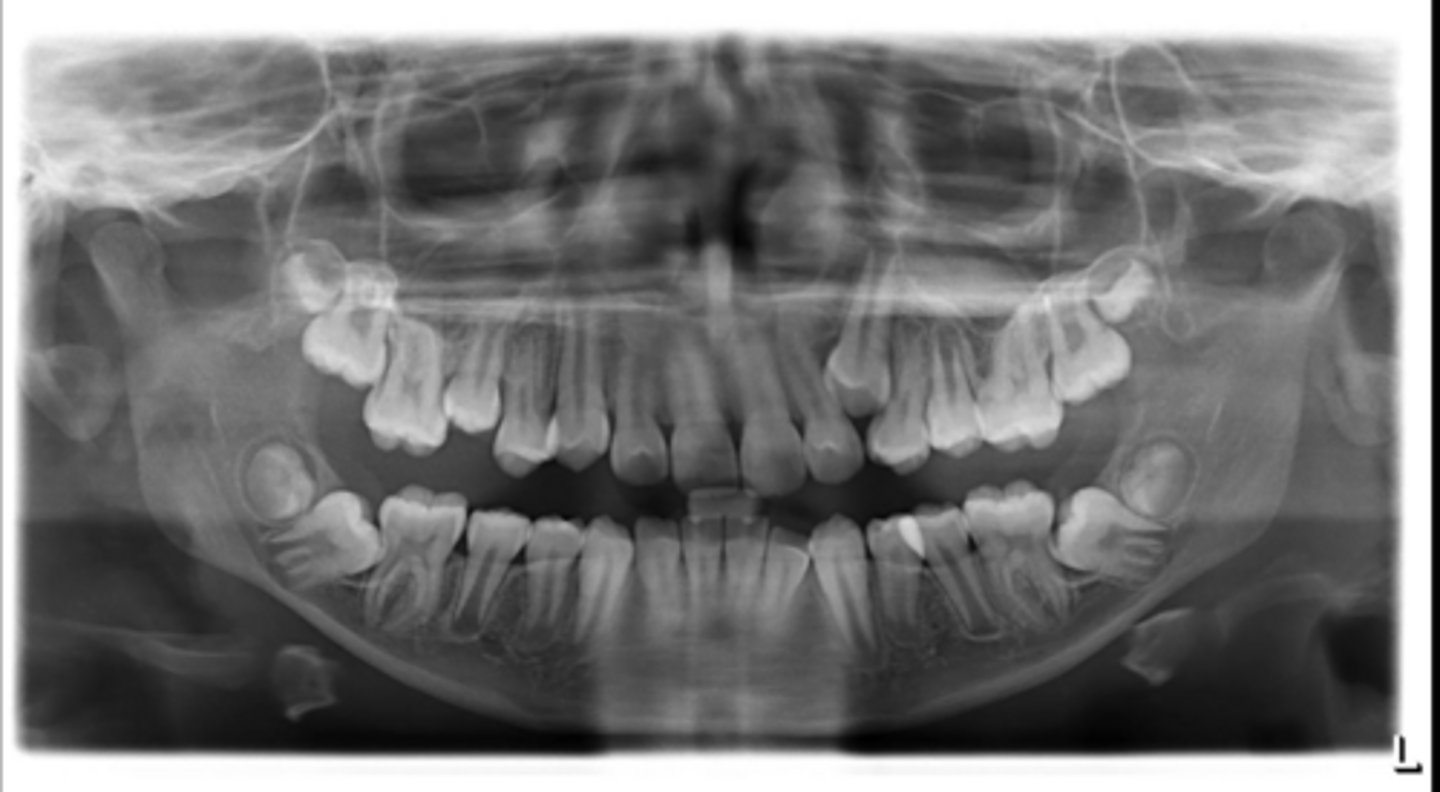

Right primary canine

Are there retained primary teeth?

Yes

Are there any impacted teeth?

Are the condyles symmetrical?

Is there a dilacerated root?

No

The mandibular left side has normal premolar/canine eruption, but the rigth side is abnormal.

Is the eruption pattern of this patient normal or not?

Are there any supernumerary teeth?

Are there any retained primary teeth?

Not at this stage

Are there impacted teeth?

Yes, within the range of normal

Symmetric condyles?

Yes - maxillary first molar

Dilacerated roots?

Yes - laterals

Are there congentially missing teeth in the maxillary arch?

Yes - an incisor

Are there congenitally missing teeth in the mandibular arch?

Yes - upper right near the premolar

Any impacted teeth?

Can't see, so can't say